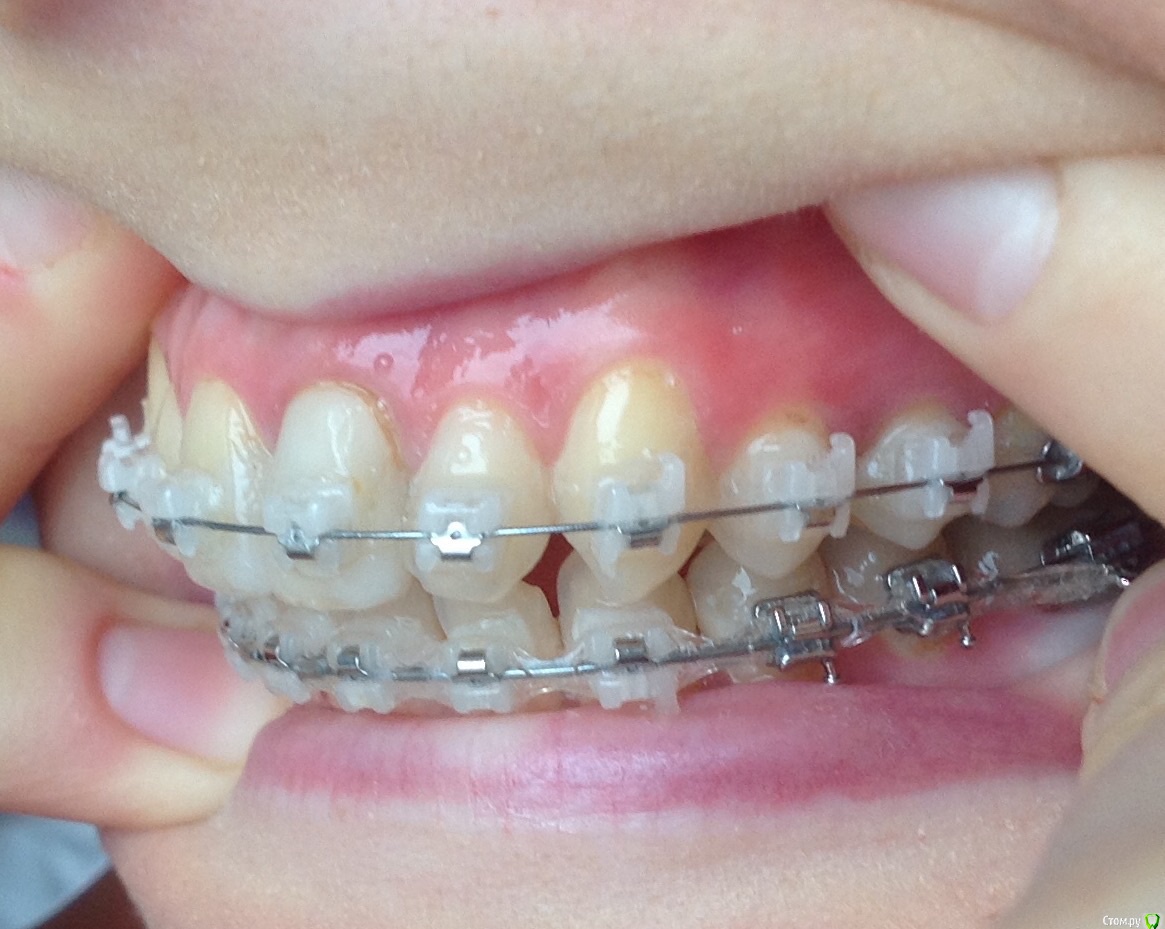

Добрый день ! Мне 29 лет. Ношу брекеты 10 мес. На данном этапе лечения сделали панорамный снимок, чтобы посмотреть ровно ли стоят корни зубов. После этого врач решил переклеить один брекет на клыке ( на снимке его видно слева ). А мне по снимку бросились в глаза , помимо этого клыка, рядом стоящий боковой резец ( он же не нравится мне как стоит и внешне) , и на нижней челюсти : 1- ый премоляр,и рядом стоящие 3 резца. Врач сказал подумать неделю и решить, хочу ли я переклеить или нет какой либо из брекетов,тк дальше они так и останутся. На её взгляд ничего переклеивать , кроме клыка, больше не нужно.

П.с. На нижн. челюсть уже поставили резинки для стягивания щелей. Я так понимаю после этого этапа уже на них брекеты не будут переклеиваться ?

Главный вопрос : Нужно ли мне переклеивать еще какие- нибудь брекеты , опускать или поднимать какой- либо из зубов, чтобы добиться большей эстетики и в дальнейшем правильного прикуса ? Или же не нужно. Заранее спасибо за внимание.